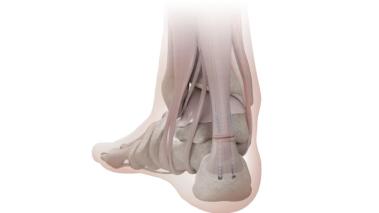

Haglund病,也称为“跟骨后滑囊炎”,表现为跟骨后上部的异常突起。这一区域与跟腱之间的滑囊,在长期的机械摩擦下,会产生炎症反应,导致疼痛、肿胀甚至局部温度升高。患者常在行走、跑步或穿着硬质鞋具时症状加重,严重时可能影响日常活动。

Haglund畸形2、Haglund病是怎么造成的?

跟骨后上方凸起的Haglund畸形,主要成因是遗传或发育因素,高弓足、跟腱紧张以及不良的步态(如用脚跟外侧着地)是常见的诱因。当穿着硬质鞋子,如皮鞋或高跟鞋时,足后跟与鞋跟之间的摩擦加剧,导致增生的跟骨对跟腱产生持续的压力和磨损,从而引发炎症,形成Haglund综合征。